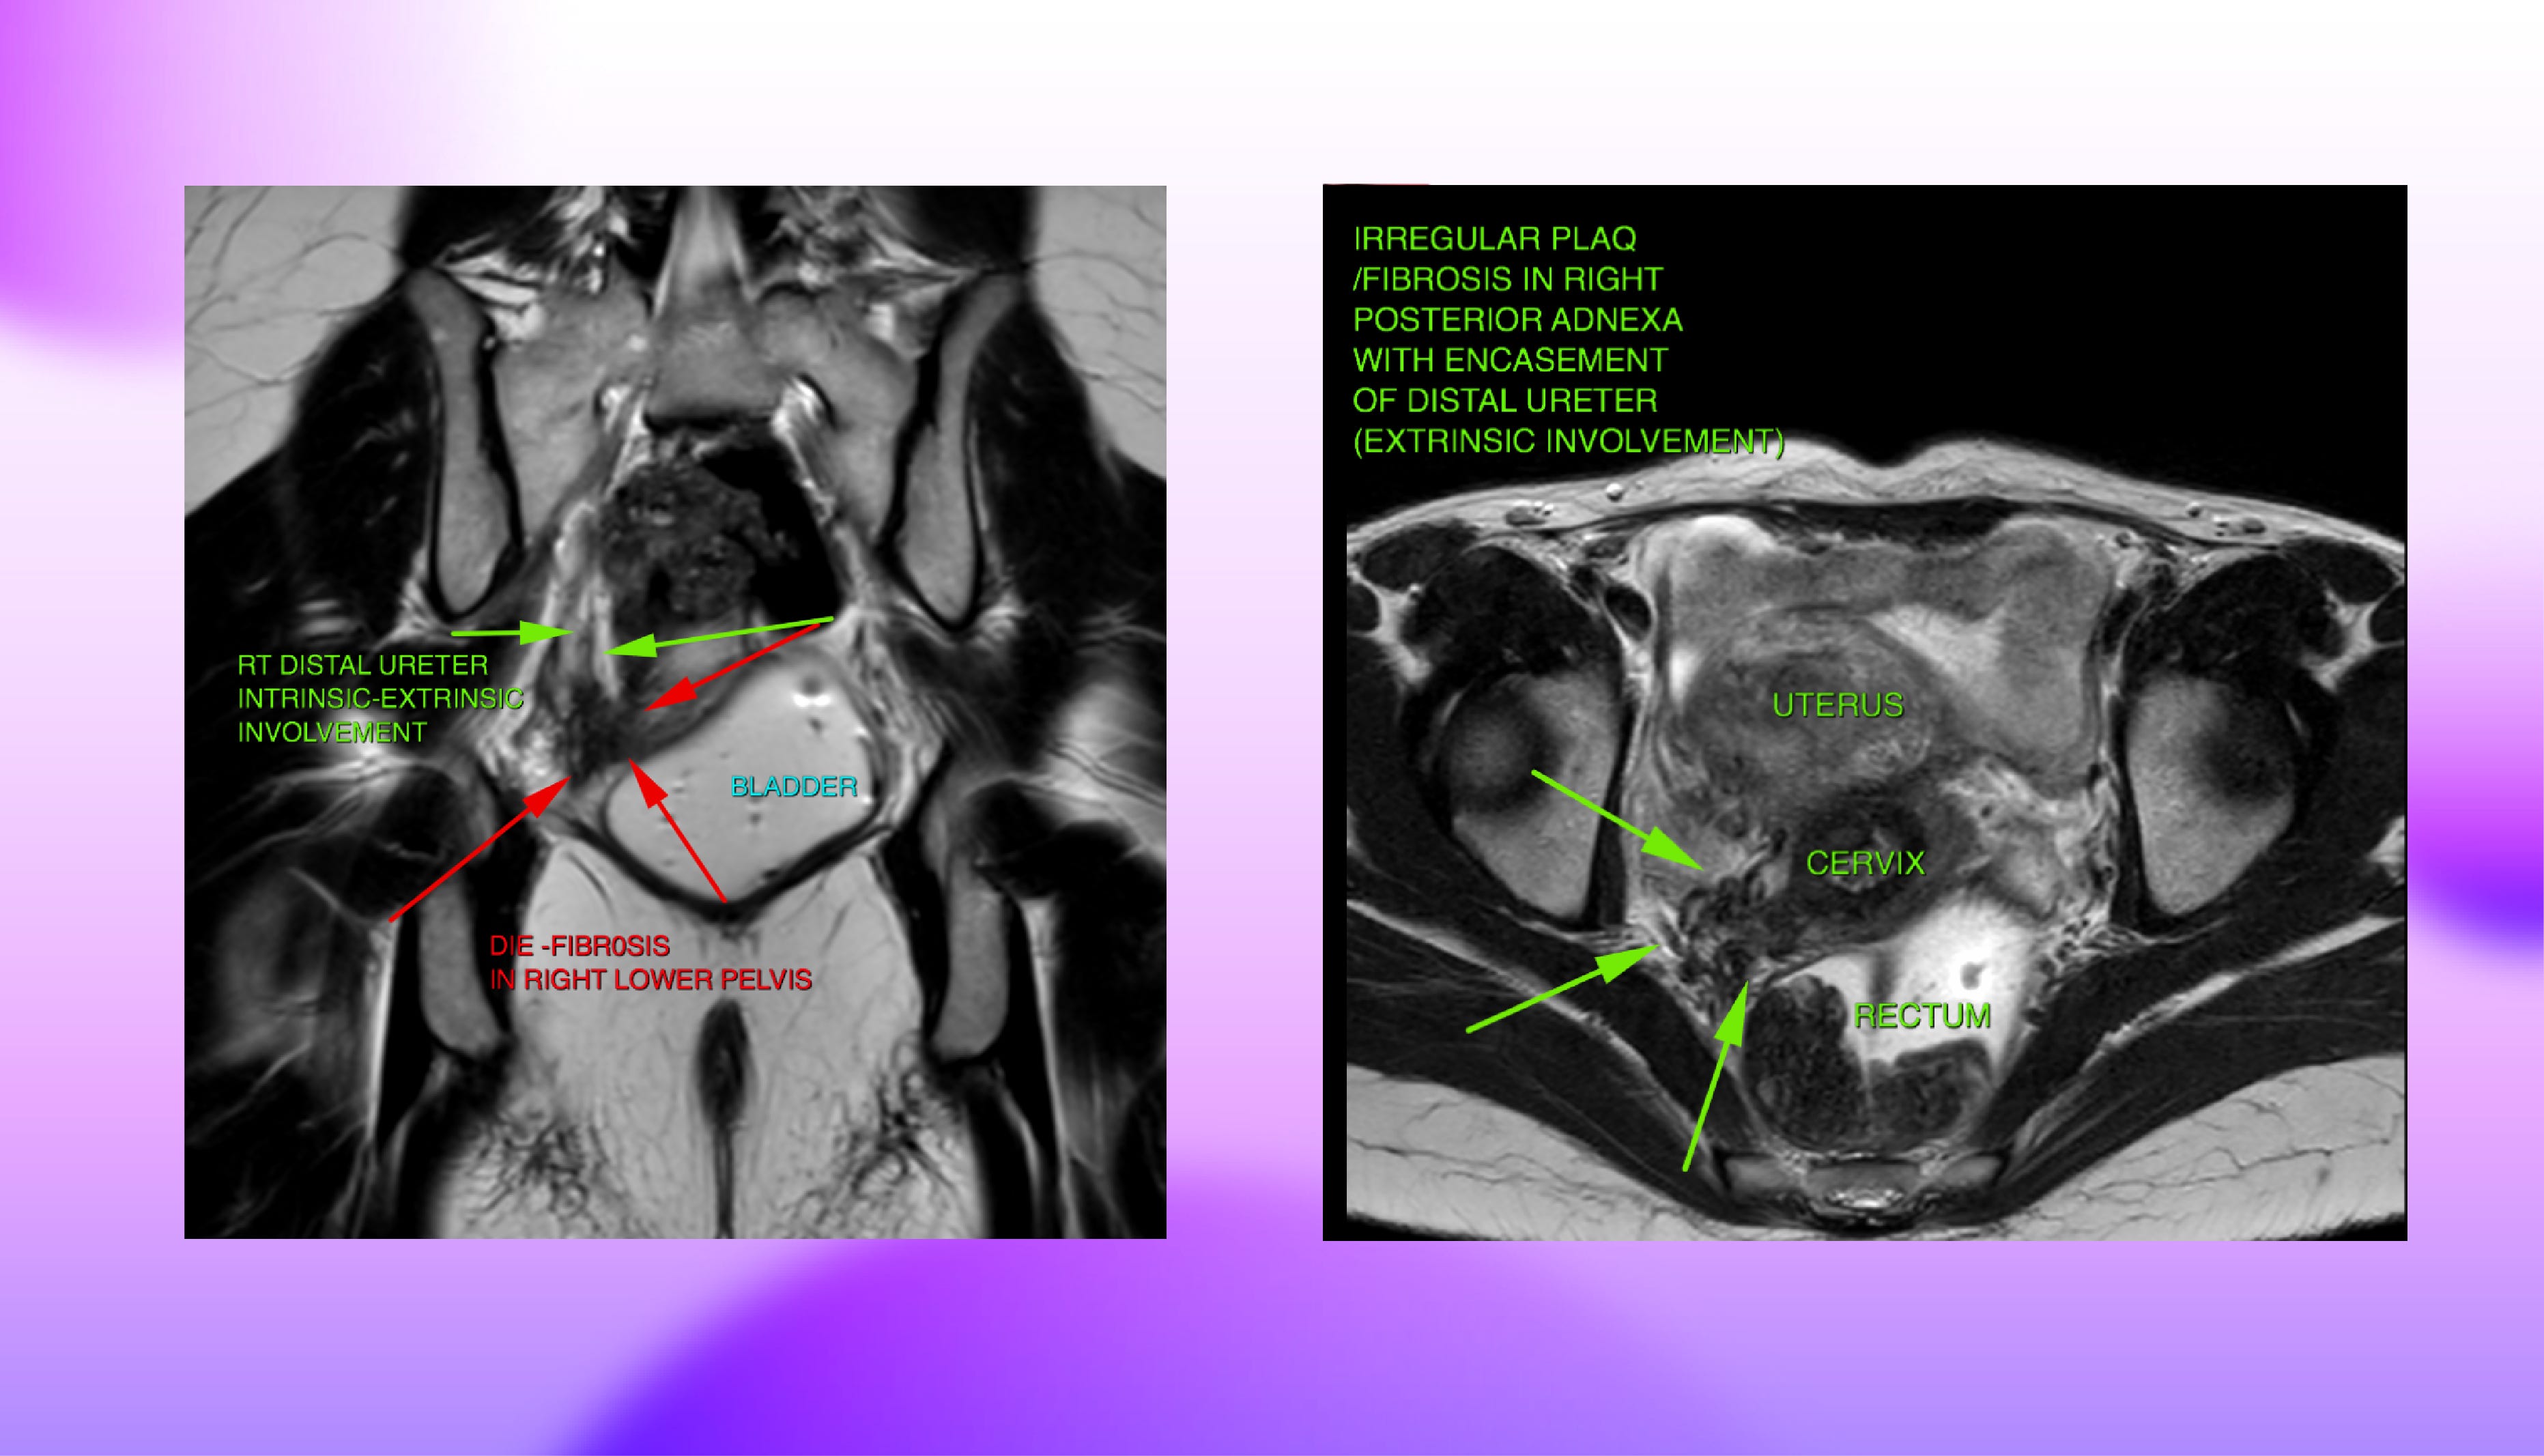

Take the ureters for instance. Observing irregular plaque or fibrosis in the right posterior adnexa in this instance of a T2 weighted axial slice shows an encasement of the distal ureter indicating extrinsic involvement of the ureter. This type of involvement typically results in tethering and angle deviation for the ureter. Whereas another T2 weighted coronal image shows both intrinsic as well as extrinsic involvement of the ureter which might lead to structuring of the lumen and hydroureteronephrosis.